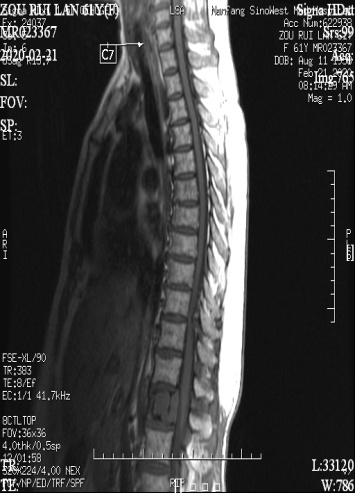

图左:术前MR示腰椎肿瘤(圆圈处)、胸椎狭窄(箭头所指)

图右:术后X光,病变脊椎切除,代以人工椎体。

手术整整进行了11个小时,在黄刚主任专业细致的操作下,邹阿姨最终有惊无险的完成了整台手术,成功对腰椎肿瘤行根治性切除,手术同时进行了胸椎板切除、椎管减压术,一并解除了邹阿姨胸椎管狭窄脊髓受压的病痛。

术中出血1500ML,远低于平均出血量,且术后疗效满意,脚底麻木完全缓解,排尿困难已解决,经过一个周期的放疗后,邹阿姨已于日前出院。